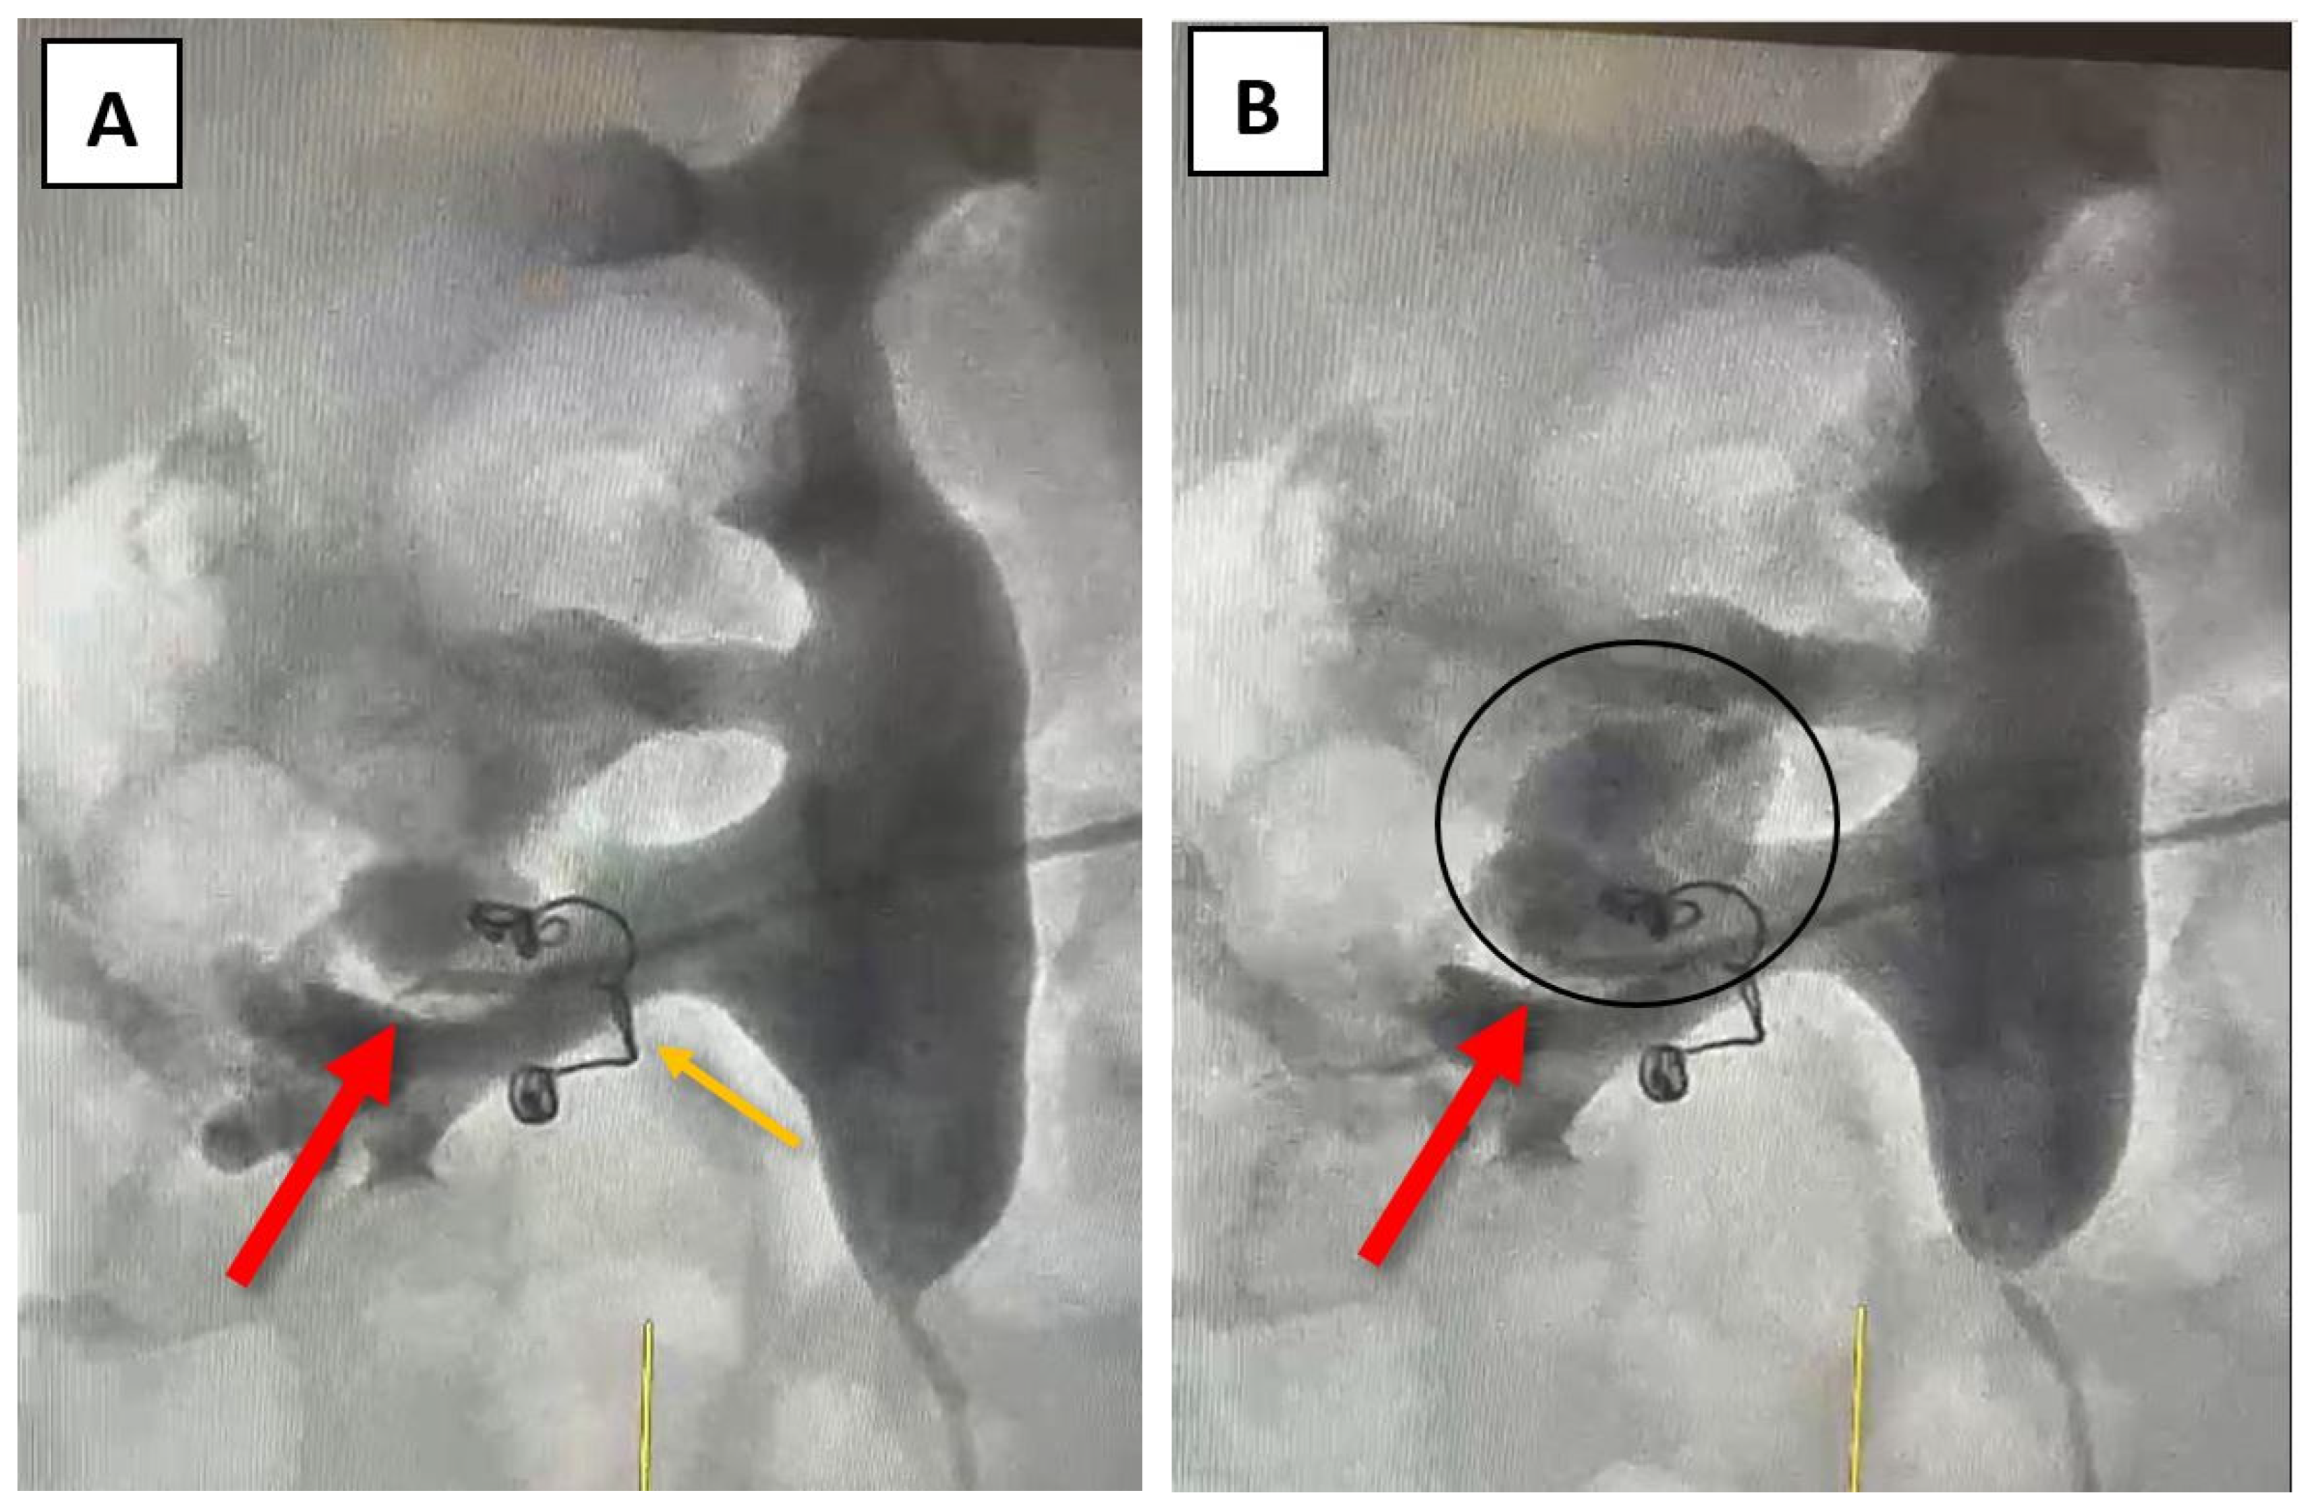

At this point, a possible fistula between an arterial vessel and the right renal pelvis was suspected, and further investigations, such as angiography, were recommended to facilitate further correlation of data. Angiography was performed through the right brachial vein using a Cobra 4F catheter. The source of bleeding was identified at the site of a small inferior renal arterial vessel after the selective administration of the contrast agent (Figure 3A,B). The coils used during the last angioembolization (eight years ago) can be observed in Figure 3.

Considering the patient’s medical history, which includes a previous selective angioembolization (SAE), our focus shifted toward identifying potential risk factors that may have contributed to or predicted the failure of the procedure. In a study that evaluated the predictive factors of SAE failure for moderate- to high-grade renal trauma, Baboudijian et al. found gross hematuria, hemodynamic instability, and urinary extravasation to be statistically significant [32]. After the first SAE, our patient did not exhibit any of these factors. In a case report published by Seno et al., another set of risk factors was identified as significant in predicting initial super-selective renal arterial embolization failure; this set includes multiple percutaneous access sites, more than two bleeding sites on a renal angiogram, and the use of a gelatin sponge alone as embolic material [3]. In our case, the patient presented with only one percutaneous access site during the initial angioembolization and a single bleeding site on the renal angiogram. During the angioembolization procedure, two coils were used (as depicted in Figure 3 – indicated by the orange arrow). Thus, none of the aforementioned situations were present in our patient’s case.

Figure 3. Angiography – (A) the source of bleeding is recognizable at the site of a small inferior renal vessel – indicated by the red arrow; (B) blush generated by the selective administration of the contrast agent – indicated by the black oval; the orange arrow indicates the two coils that were previously used for the angioembolization.